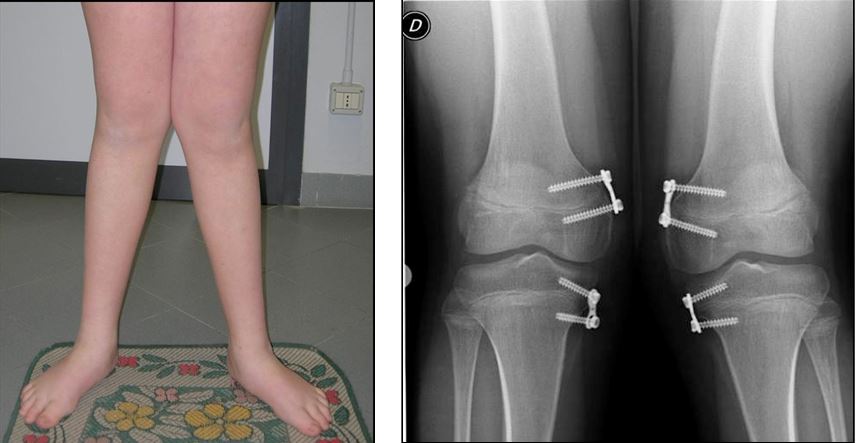

La crescita guidata risulta essere indicata anche nel trattamento di deviazioni assiali secondarie a patologie congenite (es esostosi multiple ereditarie) o metaboliche.

In questi casi, in genere, a causa dell’entità del difetto e del relativo impatto clinico la procedura viene eseguita più precocemente ed i tempi di correzione, legati al ritmo di crescita del paziente, risultano leggermente più lunghi (Fig. 4 a-b).